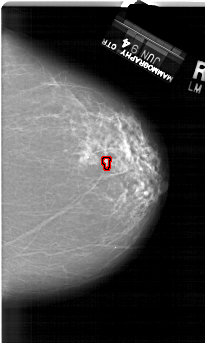

A_1503_1.RIGHT_CC

RIGHT_CC LINES 6511 PIXELS_PER_LINE 3886 BITS_PER_PIXEL 12 RESOLUTION 43.5 OVERLAY

FILE: A_1503_1.RIGHT_CC.OVERLAY

TOTAL_ABNORMALITIES 1

ABNORMALITY 1

LESION_TYPE CALCIFICATION TYPE PLEOMORPHIC DISTRIBUTION LINEAR

ASSESSMENT 4

SUBTLETY 2

PATHOLOGY MALIGNANT

TOTAL_OUTLINES 1

BOUNDARY